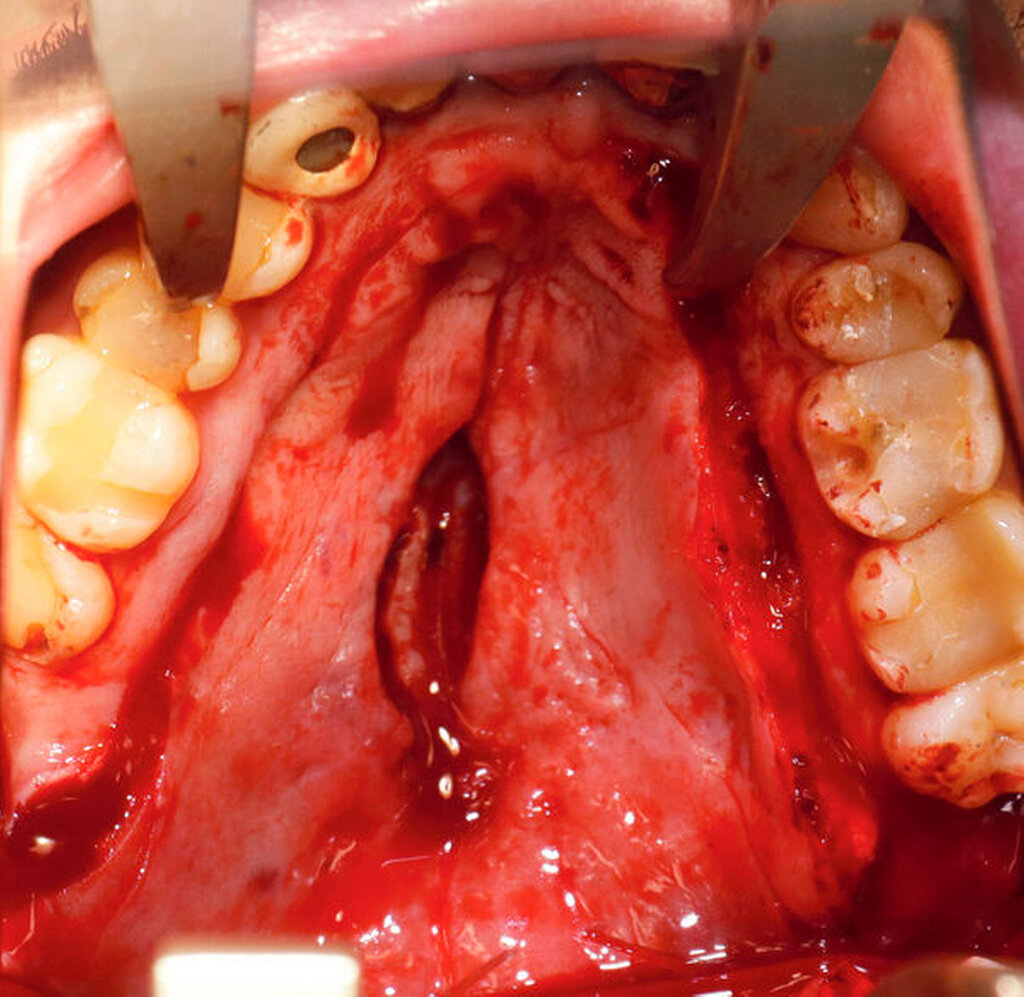

Nach vier Monaten konnten die internistische Therapie unter Remission bei einer deutlichen Besserung des Allgemeinzustands ausgeschlichen und der operative Defektverschluss geplant werden. Die zweischichtige Palatoplastik führten wir in oraler Intubationsnarkose unter stationären Bedingungen durch (Abbildungen 5–7).